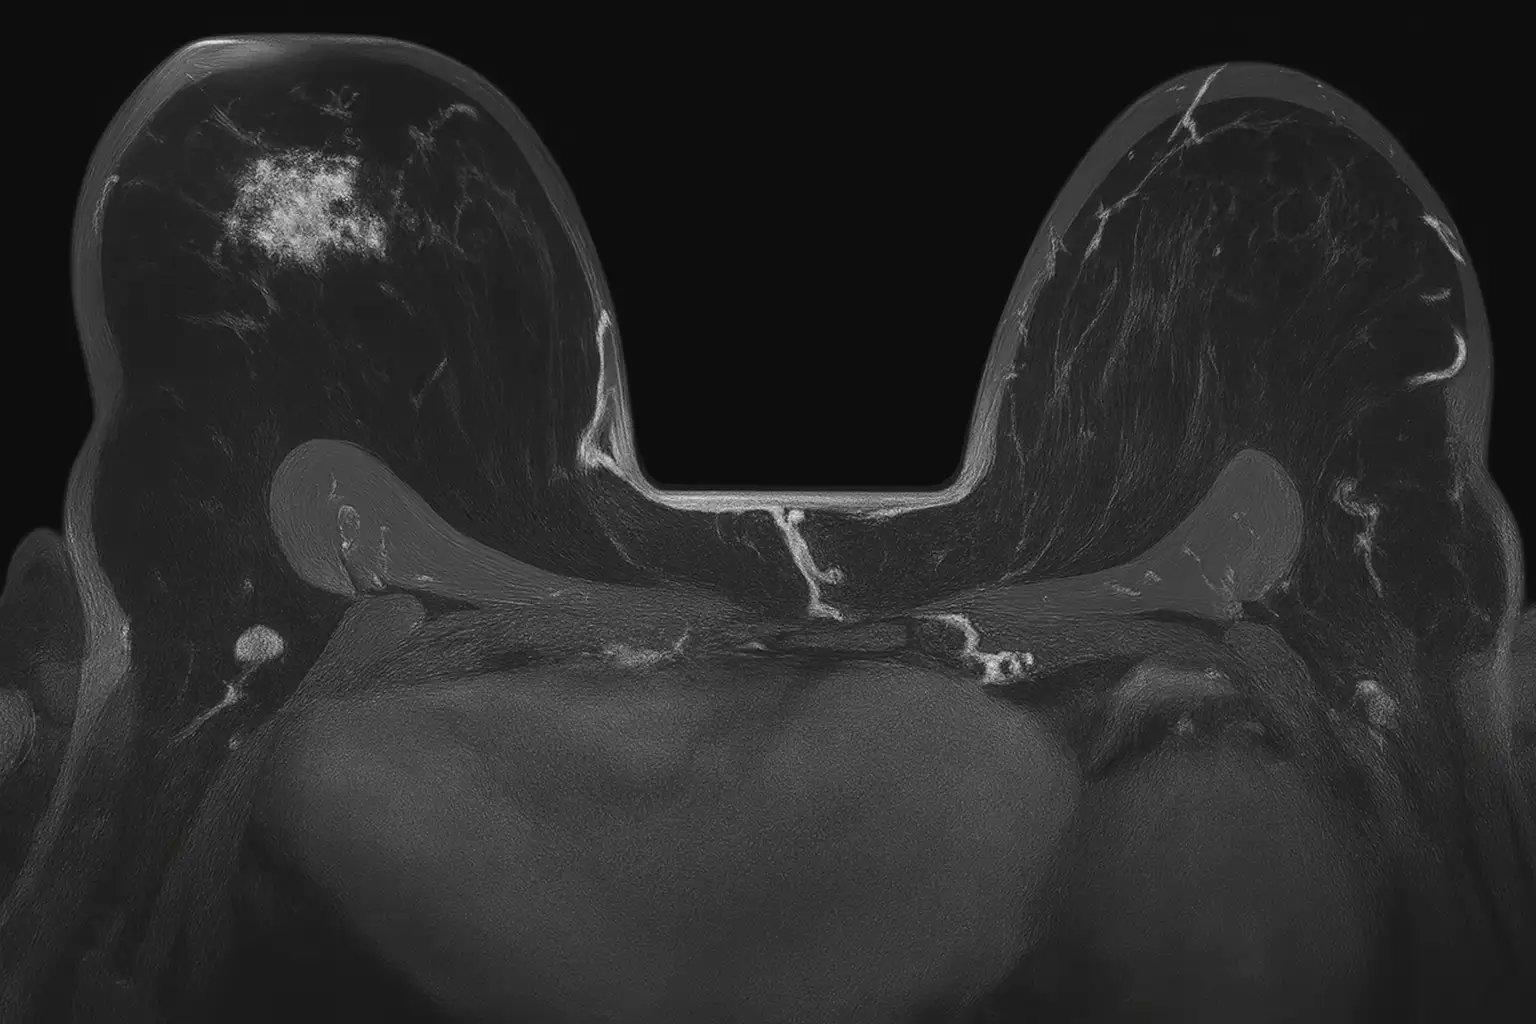

Рак молочной железы — одно из наиболее распространённых заболеваний. Чем раньше выявлена патология, тем выше вероятность полного выздоровления. МРТ молочных желез позволяет увидеть минимальные изменения ткани, недоступные при УЗИ и маммографии.

• Получение до 800 послойных снимков в трёх проекциях.